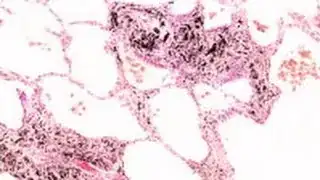

We've probably all seen photos of smokers' lungs compared to non-smokers lungs. For example:

So my question is: Are smokers' lungs visibly and routinely blackened and/or discolored in the absence of lung disease?